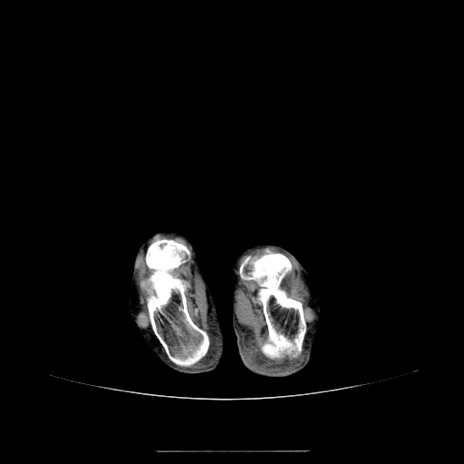

【症例】70歳代女性

【主訴】お腹が張る

【現病歴】1週間くらい前から腹部膨満の自覚あり。昨日夜から増悪したため、本日救急外来受診。

【身体所見】意識清明、BT 36.5℃、BP 165/106mmHg、HR 80bpm、SpO2 98%、腹部:膨満、軟、自発痛・圧痛なし、触診にて不快感あり、腸蠕動音:減弱

【データ】WBC 12600、CRP 1.04